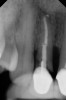

Fig 4. Radiograph showing root fracture and apical lesion of the tooth (No. 7).

Figure 4